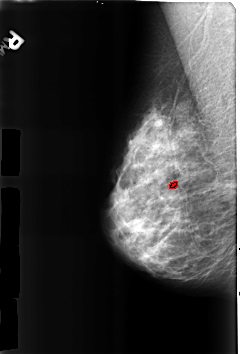

B_3184_1.RIGHT_MLO

RIGHT_MLO LINES 4600 PIXELS_PER_LINE 3112 BITS_PER_PIXEL 12 RESOLUTION 50 OVERLAY

FILE: B_3184_1.RIGHT_MLO.OVERLAY

TOTAL_ABNORMALITIES 1

ABNORMALITY 1

LESION_TYPE CALCIFICATION TYPE LUCENT_CENTERED DISTRIBUTION N/A

ASSESSMENT 2

SUBTLETY 3

PATHOLOGY BENIGN

TOTAL_OUTLINES 1

BOUNDARY